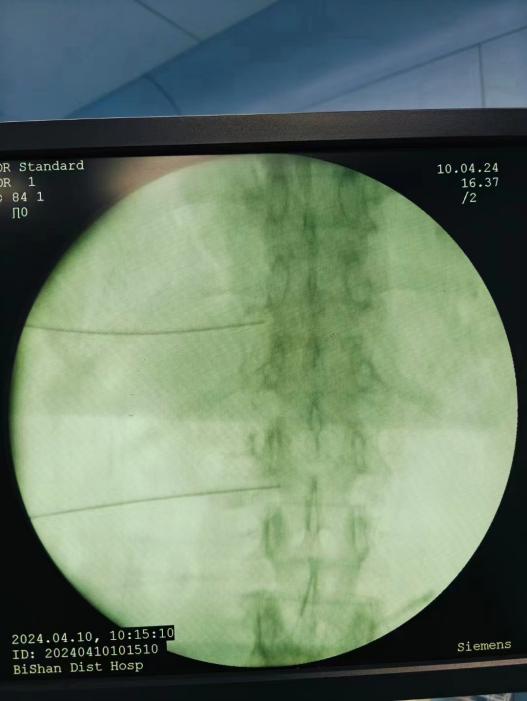

ac874aa18aee42e58f8890dd86cc1a27.Jpeg  09566eb81ad84804af008e90e5297638.Jpeg

椎間盤射頻消融術(shù)、膠原酶椎間盤化學(xué)消融術(shù)